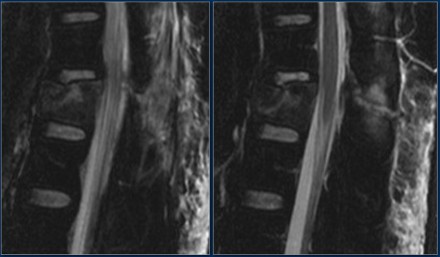

Look at the images.

What are the findings?

Then scroll to the next images.

The findings are:

- Vertebral bodies show marrow edema as a result of a fracture.

- Torn flaval ligament (yellow arrow).

- Fractures through the posterior elements (red arrows).

The TLICS-score is high, because there is distraction and injury to the PLC.